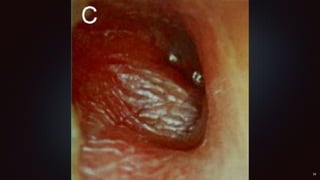

Cholestéatome

Otoscopie : PDR atticale/atriale

avec pus et squames épidermiques

(non auto nettoyante)

Masse blanchâtre « perle »

rétrotympanique

Cholestéatome Otoscopie : PDRatticale/atriale avec pus et squames épidermiques (non auto nettoyante) Masse blanchâtre « perle » rétrotympanique Examens systématique : TDM ou IRM (hyperdensité de la caisse, avec lyse ossiculaire)